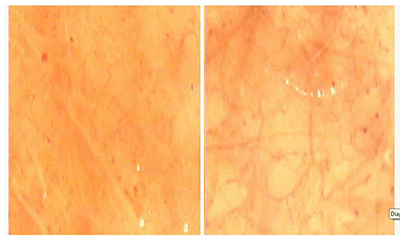

FIGURA 1 L’anidride carbonica somministrata, realizza, in concreto, un trattamento riabilitativo della microcircolazione esplicando i suoi effetti sui fattori che regolano a breve termine il flusso ematico tessutale locale come la CO2 prodotta dal metabolismo cellulare. Si verifica un incremento della sfigmicità arteriolare e metarteriolare ,un rilassamento delle fibrocellule muscolari lisce degli sfinteri precapillari, un aumento della deformabilità eritrocitaria. La conseguenza di tali effetti è un incremento della velocità e della entità del flusso ematico tessutale locale. L’aumento della velocità, della entità del flusso ematico tessutale locale, della sfigmicità arteriolare e metarteriolare sono stati rilevati mediante videocapillaroscopia a sonda ottica (VCSO) (Albergati e al., 1997) (Fig. 2) e mediante Laser Doppler Flow (LDF) (Albergati e al., 1997) (Fig. 3).

FIGURA 2

Figura 2 Microcircolazione pre-carbossiterapia e post-carbossiterapia (immagini VCSO) - By Albergati F., Parassoni L., Lattarulo P., Varlaro V., Curri S.B.: Carbossiterapia e vasomotion: comparazione tra immagini videocapillaroscopiche e referti Laser doppler flow dopo somministrazione di anidride carbonica. Riv. La Medicina Estetica, anno 21, n.1, gennaio-marzo 1997. Editrice Salus Internazionale, Roma